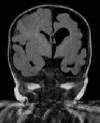

Prenatal ultrasonographic detection of unilateral cerebral ventriculomegaly arises suspicion of pathological condition related to cerebrospinal fluid flow obstruction or cerebral parenchimal pathology. Dyke-Davidoff-Masson syndrome is a rare condition characterized by cerebral hemiatrophy, calvarial thickening, skull and facial asymmetry, contralateral hemiparesis, cognitive impairment and seizures. Congenital and acquired types are recognized and have been described, mainly in late childhood, adolescence and adult ages. We describe a female infant with prenatal diagnosis of unilateral left ventriculomegaly in which early brain MRI and contrast enhanced-MRI angiography, showed cerebral left hemiatrophy associated with reduced caliber of the left middle cerebral artery revealing the characteristic findings of the Dyke-Davidoff-Masson syndrome. Prenatal imaging, cerebral vascular anomaly responsible for the cerebral hemiatrophy and the early clinical evolution have never been described before in such a young child and complete the acquired clinical descriptions in older children. Differential diagnosis, genetic investigations, neurophysiologic assessments, short term clinical and developmental follow up are described. Dyke-Davidoff-Masson syndrome must be ruled out in differential diagnosis of fetal unilateral ventriculomegaly. Early clinical assessment, differential diagnosis and cerebral imaging including cerebral MRI angiography allow the clinicians to diagnose also in early infancy this rare condition.